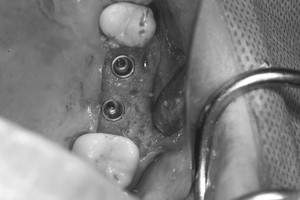

口腔内写真

- Befor

- After

| 年齢 | 50代・男性 |

|---|---|

| 主訴 | 部位:左下6番7番 主訴:左下奥歯腫れて痛い。 |

| 治療内容 | 左下6番抜歯、左下6番7番骨造成、インプラント埋入 |

| 治療費 | 合計:1,232,000円 ・内訳 診断料:55,000円 サージカルガイド2本:66,000円 GBR:110,000円×2本 埋入料:165,000円×2本 静脈内鎮静麻酔:77,000円 2次OPE:22,000円×2本 仮歯:55,000円×2本 上部構造(フルジルコニア):165,000円×2本 (2023年1月現在) |

| 治療期間 | 約8ヶ月 |

| リスク・副作用 | リスク・副作用 |

| 治療方針 | 元々支台歯に負荷がかかりやすいとされている延長ブリッジを抜歯し、1本単体でしっかりかめるようにインプラントを2本埋入した。骨吸収も進んでいたため、※GBR法で骨造成を同時に行った。 治療と並行して、全顎的な歯周病治療も行い、今後は歯周病が進行しないよう、こまめにメンテナンスに通っていただく。 |

| 特記事項 | ※1 GBR・・・骨再生誘導法。骨の高さや厚みを人工骨や人工膜などを使用し再生する方法 |

| 担当者所見 | 6番は歯根分割された被せ物が7番の欠損部との延長ブリッジとされており、強い咬合と歯周病も相まって負荷がかかり動揺し、歯として機能しなくなったため、抜歯となった。 |